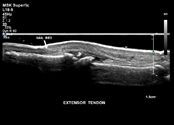

general-imaging.pdf